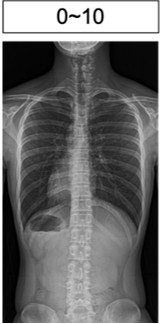

コブ角 0-10度

0~10°